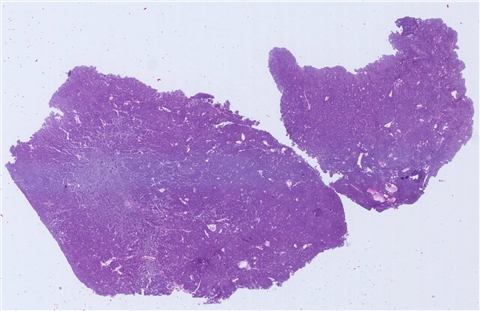

案例12 (7303)

性别:       年龄:71

患者详情: 右下腹痛7月余。CT:回盲部占位,考虑恶性占位,伴周围淋巴结战役,肝多发转移。血CEA及CA199正常。

大体所见: 送检结肠长为8cm,小肠长为5cm,于回盲部见一肿物,大小为4.5*4*1.8cm,灰白,部分质硬,部分质中。

医院: 中山大学附属肿瘤医院